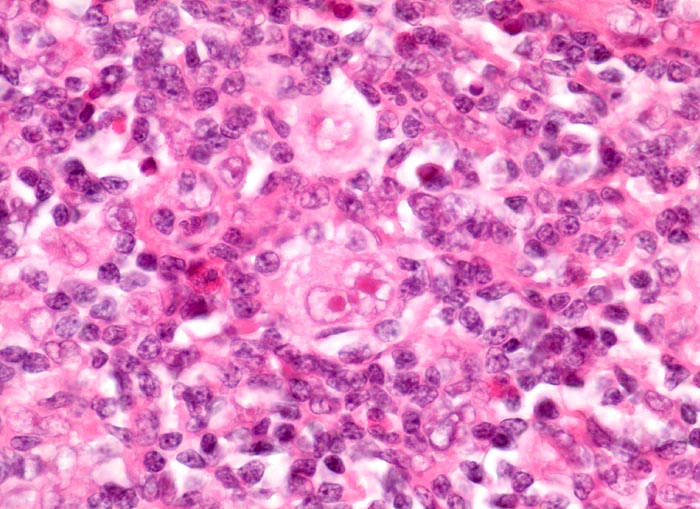

Morphologische Merkmale:

• Zerstörung der Lymphknotenarchitektur.

• Von breiten Bindegewebssträngen abgegrenzte Knoten.

• Die Knoten bestehen vorwiegend aus einem Mischzellinfiltrat reaktiver Zellen: Lymphozyten, Histiozyten, eosinophile Granulozyten und Plasmazellen.

• Reed-Sternbergzelle mit spiegelbildlich angeordneten Kernen mit sehr grossen eosinophilen Nukleolen.

• Einkernige Hodgkinzelle mit prominentem Nukleolus umgeben von einem Retraktionsartefakt (Lakunarzelle).